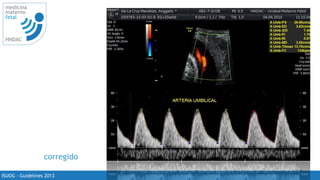

corregido

ISUOG - Guidelines 2013